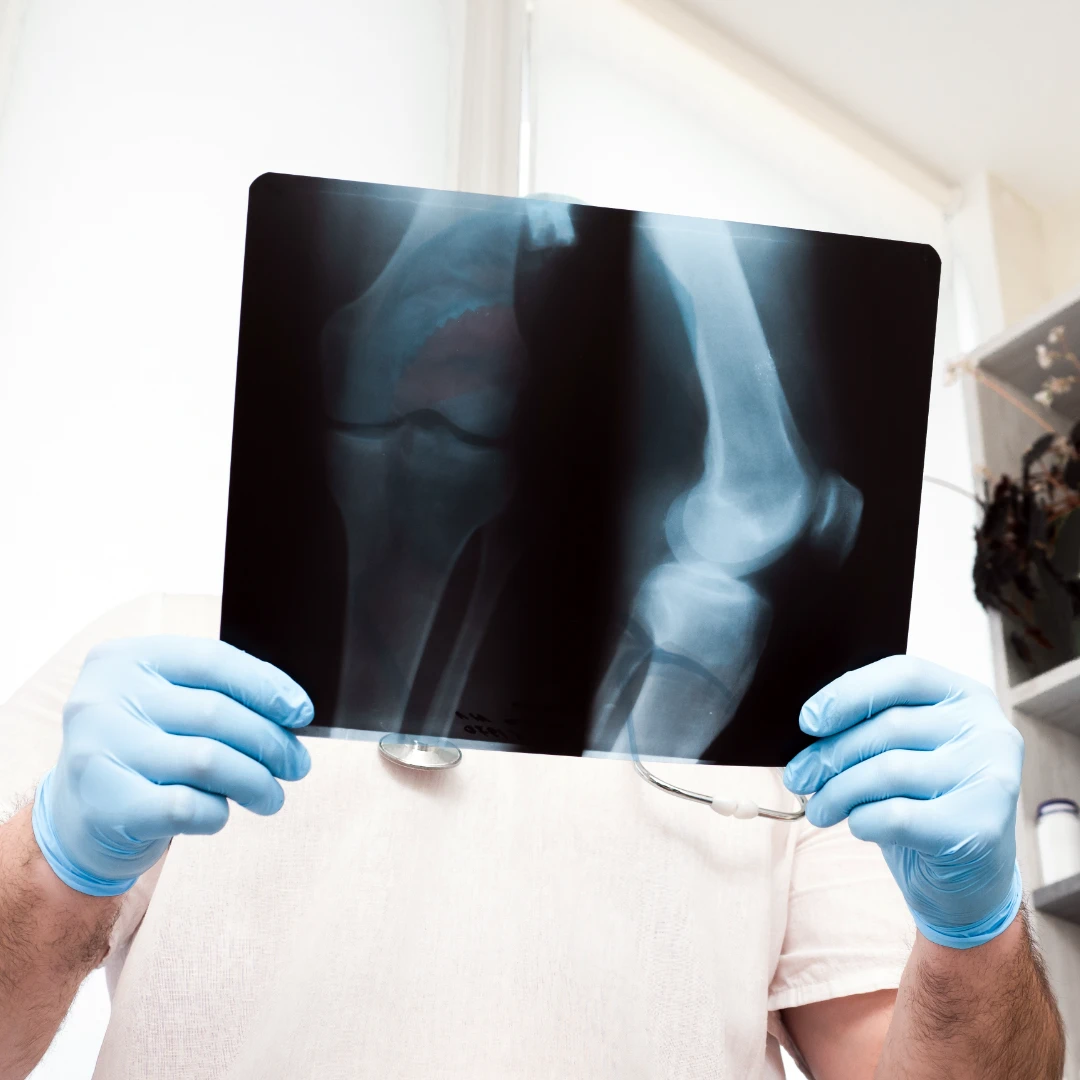

Bone/joint X-ray: effective in visualising the bone and joint structures of the upper and lower limbs. It is the main medical modality to diagnose bone fractures and joint dislocations.